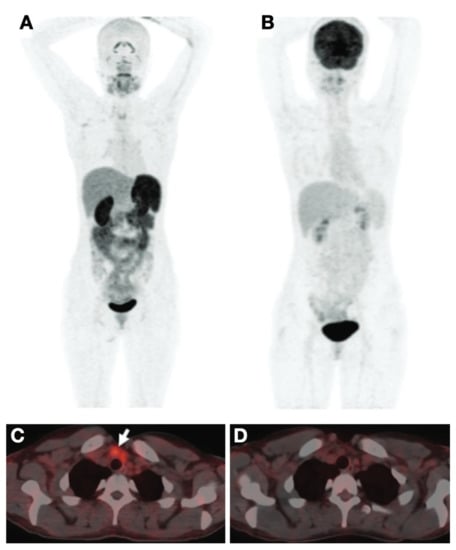

- Ho, A.L.; Grewal, R.K.; Leboeuf, R.; Sherman, E.J.; Pfister, D.G.; Deandreis, D.; Pentlow, K.S.; Zanzonico, P.B.; Haque, S.; Gavane, S.; et al. Selumetinib-Enhanced Radioiodine Uptake in Advanced Thyroid Cancer. N. Engl. J. Med. 2013, 368, 623–632. [Google Scholar] [CrossRef]